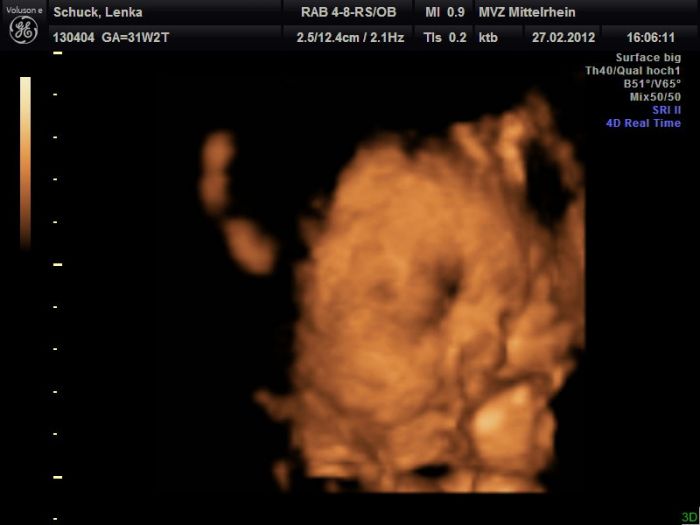

Tak dnes to vyšlo :)) Sice ne úplně dokonale, ale byl to poslední pokus, tak lepší než nic :))) Malej už je holt moc velkej...

Leno,moc hezký fotečky,je vidět,že u je mu tam už těsno.Jinak Maruško už mám13 kg nahoře.

Lenulko ten je krásnej

Dík holky :)) Ale zase jsem měla o 2 kila míň, než posledně :D Já furt hubnu a z malýho roste otesánek :D